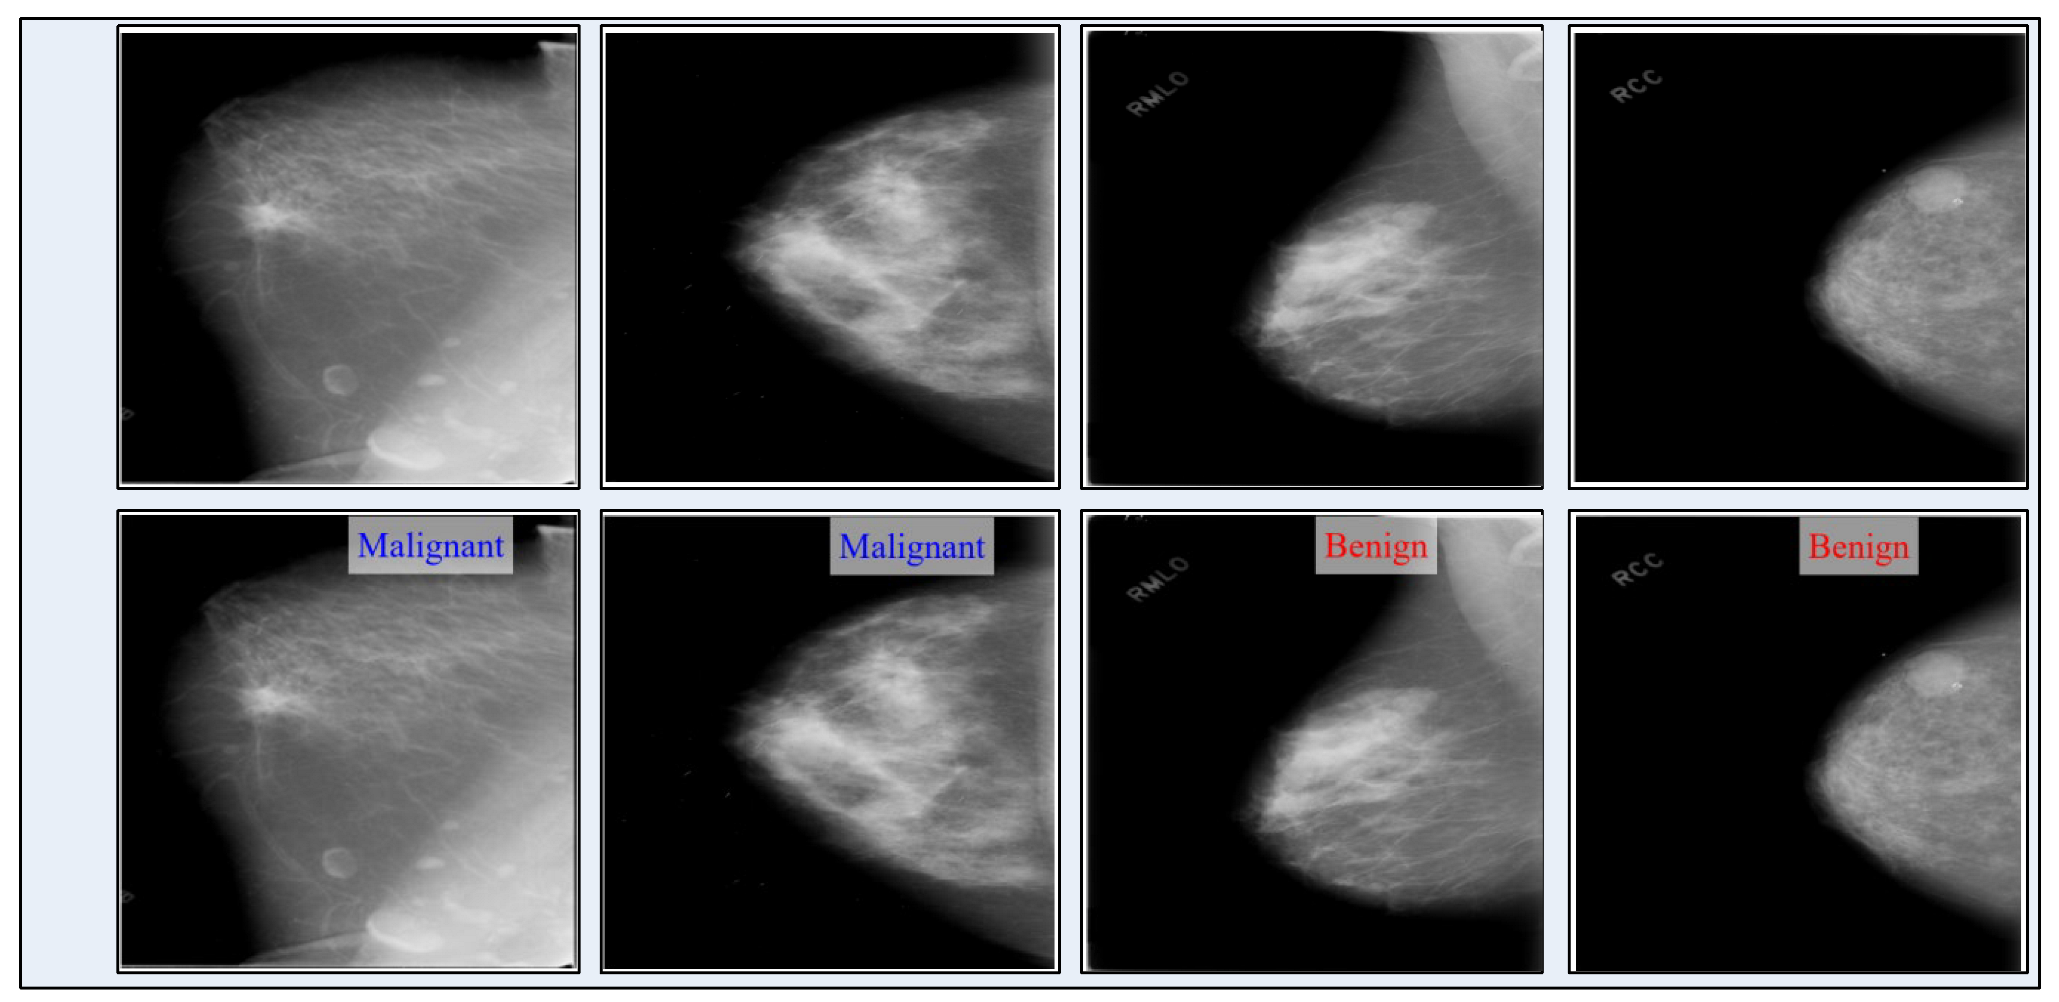

2.1. Dataset Collection

3.8. Visual Facts